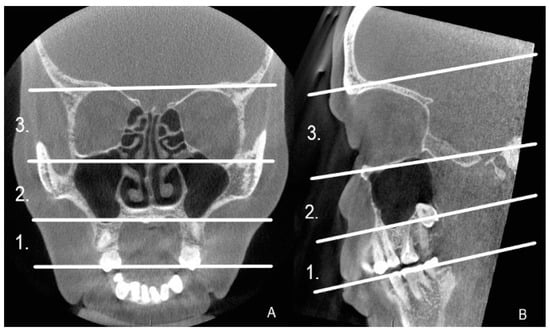

All the CBCT images were re-reviewed by two radiologists: one specialized in oral and maxillofacial radiology and the other in head and neck radiology. The referrals and medical reports were re-checked to ascertain the diagnosis or the suspicion of CRS, and the etiology of the infection. The magnitude of the artifact was analyzed visually and the following question was considered: does it disturb the recognition of the anatomy and can a diagnosis of infection be made? (yes/no). The artifacts were analyzed in three cross-sectional views, axial, sagittal, and coronal, and in three horizontal levels as shown in Figure 1. The horizontal levels were delimited by anatomical landmarks, and in each CBCT image, the artifacts were recorded at all individual levels. An artifact was recorded as complicating the diagnosis, even when the diagnosis was impaired only in one slice of the one cross-sectional view of the CBCT image.

Analyzing the anatomy in the dentoalveolar area of the maxilla, at level 1 (Figure 1), required the recognition of the periodontal ligament space surrounding the premolar and molar roots, and endodontic fillings including the root canal posts were necessitated. Implants and dental crowns were recognized by their structure and shape in the CBCT images. A dental filling on the mesial, occlusal, and buccal sides of the tooth was defined as a large dental filling. Different materials such as amalgam, composite, or ceramic could not be differentiated in the CBCT images. AP of the maxillary premolar or molar was diagnosed when a distinctly widened periodontal ligament or a radiolucent lesion was identified in the periapical area of the root. To analyze the anatomy of the maxillary sinus at level 2 (Figure 1), the cortex of the sinus walls, particularly the maxillary sinus floor, had to be visible. A mucosal thickening of 2 mm or more was needed to make the diagnosis of sinusitis. The same criteria were required for the other paranasal sinuses at level 3 (Figure 1).

We re-examined all 214 CBCT images to analyze the location and prevalence of all artifacts, even the minor ones, in more detail. All artifacts were recorded in three cross-sectional views, axial, sagittal, and coronal, and in three horizontal levels, as given in Figure 1. As expected, artifacts of any degree were most common at level 1, present in all 214 images. Level 2 artifacts were less frequent, present in 60/214 (28%) of the CBTC images. At level 3, covering the sphenoid, ethmoid, and frontal sinuses, artifacts were recognized in only one image (0.5%) due to a metal plate in the maxilla (Figure 3). Artifacts were equally seen in all coronal, axial, and sagittal views. We also analyzed the interobserver reliability to detect artifacts. In total, 50 CBCT images were selected randomly to calculate the overall agreement of the interobserver reliability. The overall agreement to identify artifacts at level 1 was almost perfect, 0.960, 95% CI 0.90–1.00 (48 out of 50); at level 2, substantial, 0.560, 95% CI 0.42–0.69 (28 out of 50); and at level 3, also almost perfect 0.940, 95% CI 0.87–1.00 (47 out of 50).

Figure 1. Coronal (A) and sagittal (B) view of the CBCT image divided in levels 1–3. 1. The area of the premolar-molar teeth and the alveolar ridge of the maxilla. 2. The area from the maxillary sinus floor to the orbital floor. 3. The area from the orbital floor to the orbital roof.